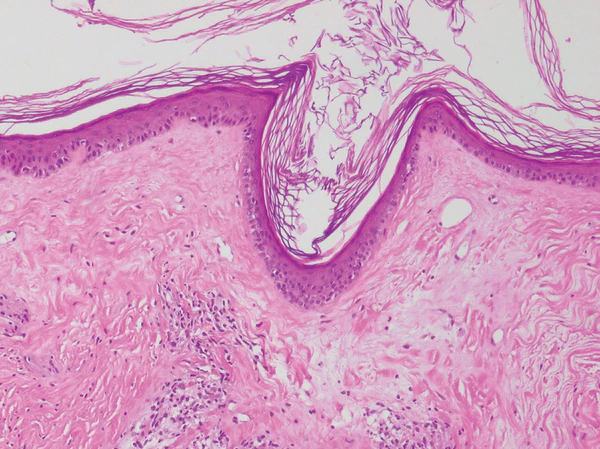

Гистологическое исследование биопсийного материала кожи выявляет характерные изменения. К ним относятся гиперкератоз, акантоз, вакуольная дистрофия клеток эпидермиса, дегенерация базального слоя, утолщение и гиалинизация дермы, снижение содержания эластических волокон, гомогенизация коллагеновых волокон, расширение кровеносных сосудов и наличие лентовидного лимфогистиоцитарного инфильтрата[1][4].